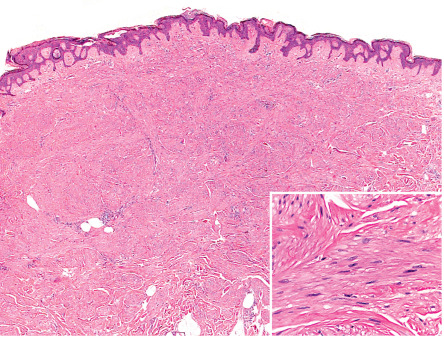

Piloleiomyomas are typically centered within the reticular dermis, with focal extension into the subcutaneous fat in some cases. They are composed of interlacing fascicles of relatively bland smooth muscle cells (myocytes), which peripherally tend to ramify between surrounding dermal collagen bundles ( Fig. 117.4 ); often there is a close relationship to hair follicles . Occasionally, the overlying epidermis is hyperplastic. Smooth muscle cells have abundant brightly eosinophilic cytoplasm and blunt-ended, cigar-shaped nuclei.

Mitotic figures are rare. In the presence of bland cytology, one or two morphologically normal mitotic figures per 10 high-power fields may be seen, which does not signify aggressive behavior. Cases with nuclear pleomorphism and atypical nuclei, but without mitotic activity (symplastic leiomyomas), have also been described .